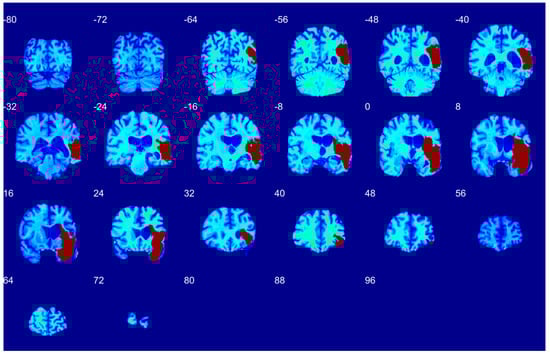

3.1. Qualitative Performance

3.2. Quantitative Performance